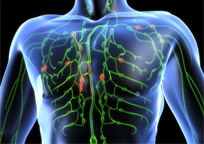

CDT & MLD Continued...

Dependent on your diagnosis, you may receive intensive therapy via daily MLD treatments and multi-layered bandaging during initiation of services. However, once you have reached the maintenance phase, the frequencies of MLD treatments are reduced and the recommendation of compression garments is provided.

Compression Therapy is essential in the management of Lymphedema and will assist in diminished swelling long term. It can maintain and enhance the results achieved by MLD. Compression therapy may need to be utilized 24 hours a day, however once the edematous limb stabilizes a compression garment is initiated.